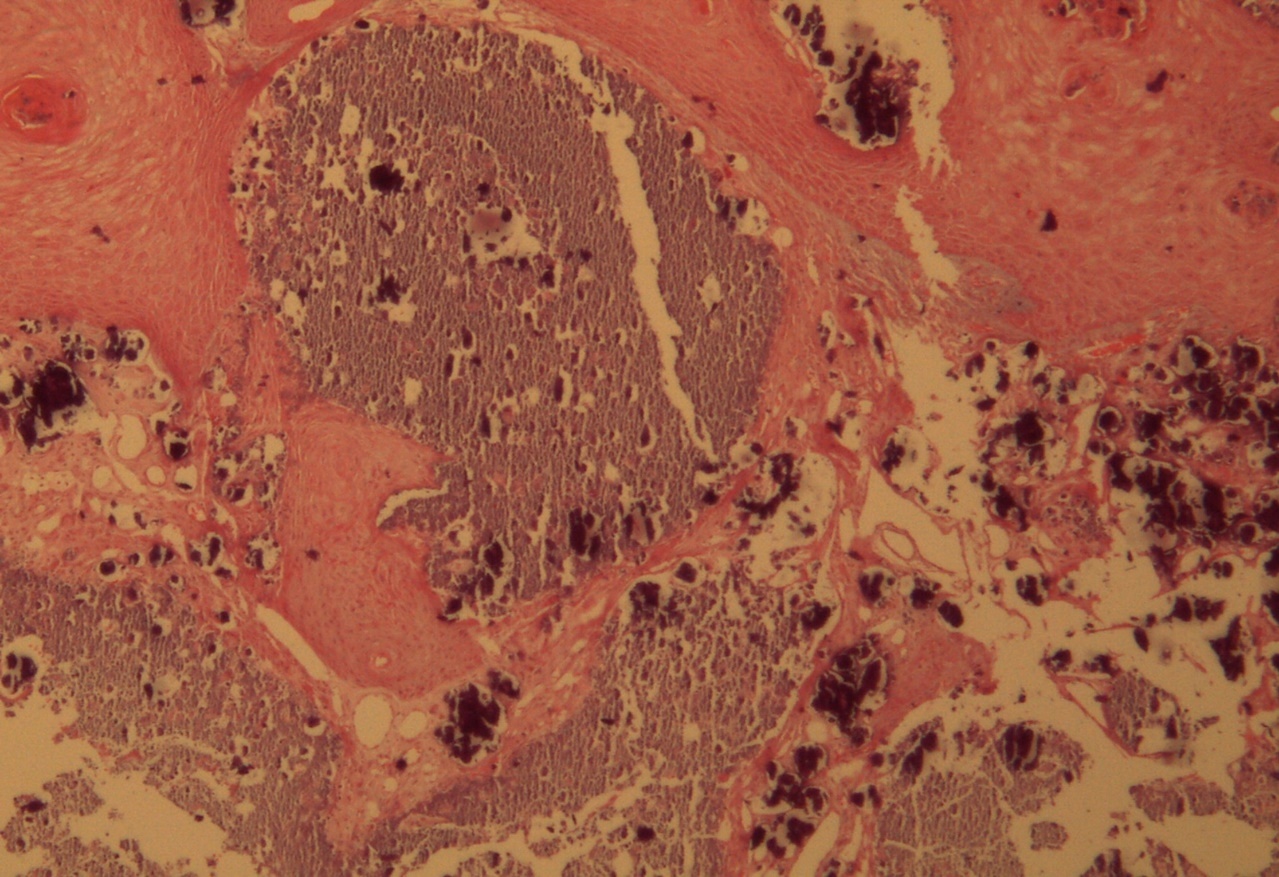

A 9-year-old male patient who was treated in the dermatology service for a progressively growing keratotic nummular dermal lesion on the right knee. With the clinical judgment of viral wart, the lesion was removed. In the Pathology Service, a nummular keratotic lesion of 0.5 cm in maximum dimensions was received, which crackled when cut. Figure 1, Figure 2, Figure 3, Figure 4, Figure 5

Figure 4.Presence of calcium deposits in the dermal vessels. Detail. HE 400x.